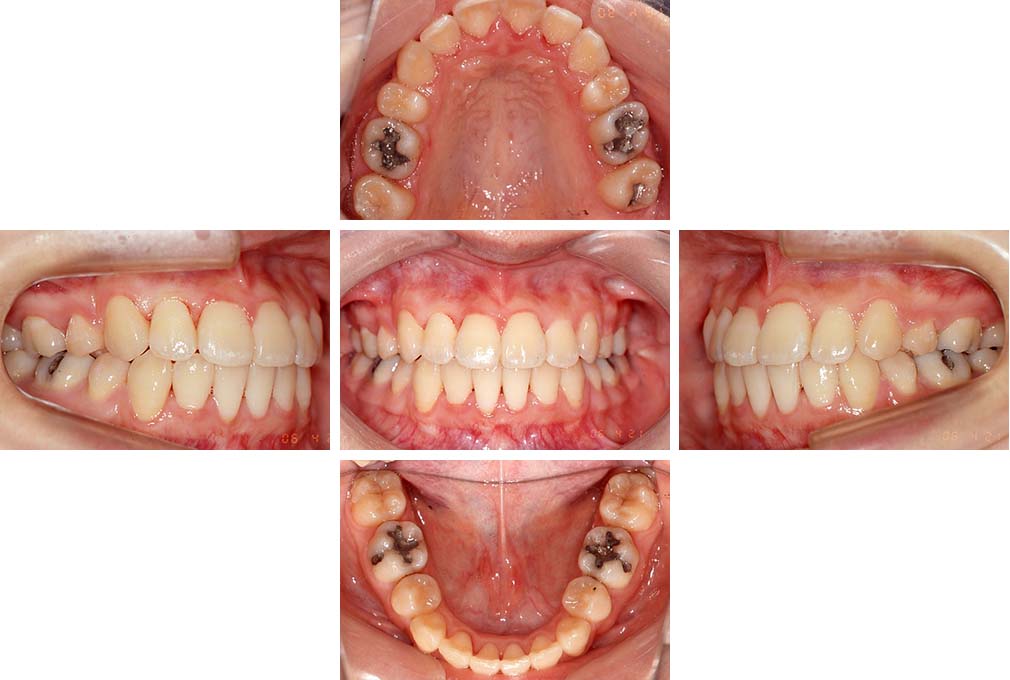

CASE:02

下顎前歯部叢生、小臼歯4歯先天欠損

初診時年齢 14歳3か月

性別 女性

治療費の目安 70万円(治療開始時)

上顎左右側小臼歯3歯、下顎左側第二小臼歯の先天欠損と下顎前歯の叢生を主訴として近隣一般歯科から紹介来院した。

上顎左側第一、第二小臼歯、右側第一小臼歯、下顎左側第二小臼歯が先天欠損であったが、左上第二乳臼歯の根の吸収がほぼ無いことから、これを残すこととして、下顎左側乳臼歯と、右側第二小臼歯を抜歯していただきマルチブラケット装置を使用して動的治療を行った。矯正用ゴムなどの協力状態も良く2年0カ月(調整来院19回)で装置を撤去し保定へ移行した。動的治療終了13年2カ月での来院時には下顎左右側智歯が萌出していたが、垂直的に萌出していたため抜歯は行っていない。

治療前

14歳3か月

治療後

動的治療期間2年0カ月

16歳7か月

13年経過

動的治療終了後13年2カ月

30歳0か月